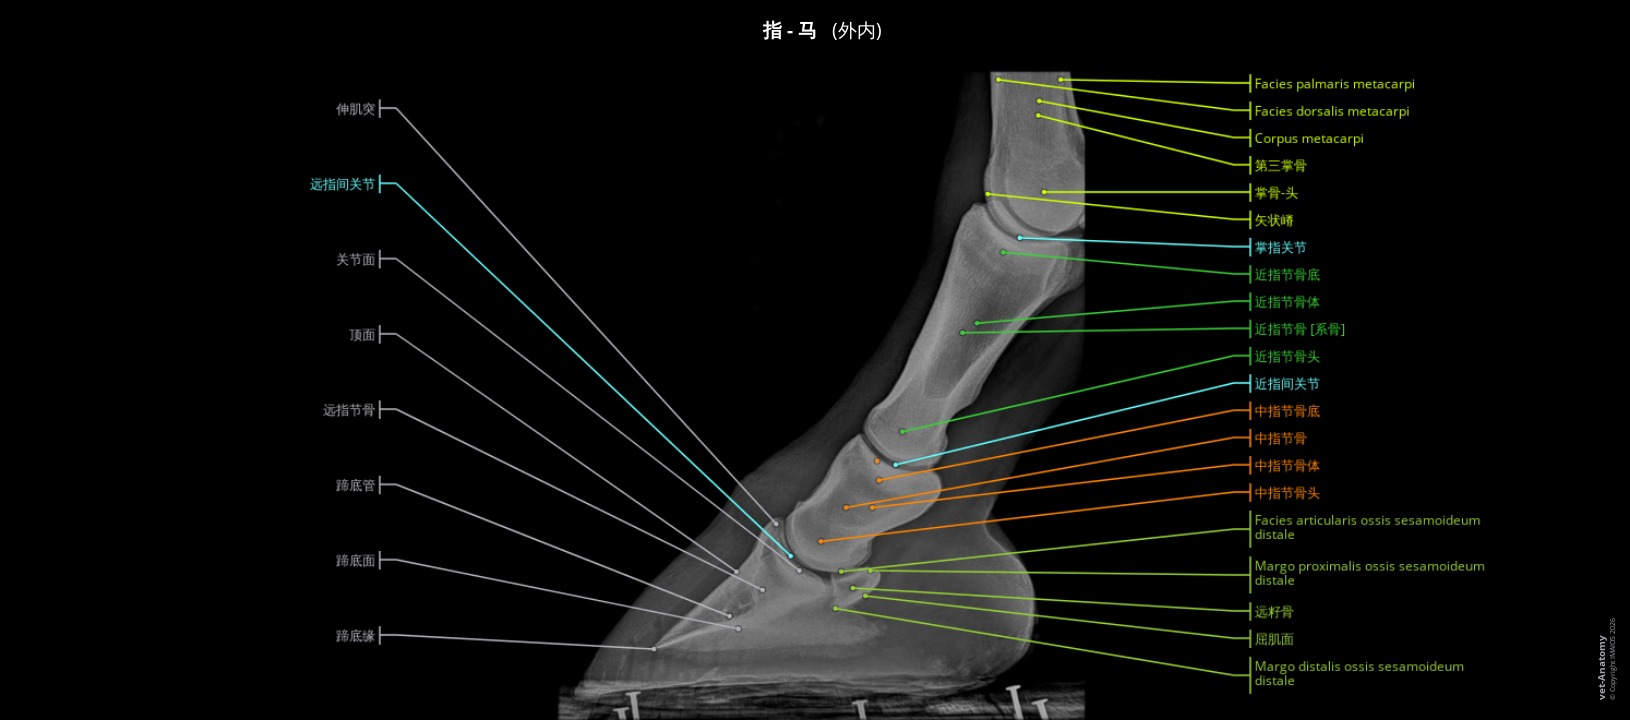

放射照相是常用于马匹的成像方式,特别是在出售或跛行诊断时:如结合超声检查,甚至CT和MRI,它可以准确和早期诊断病变,特别是骨关节病。

解读放射线图像必需有良好的解剖学知识。此单元是为学生、兽医从业者和放射科医生提供关于成年马的正常放射学解剖基本信息。

材料与方法

这些放射检查采用最常见的发病情况,由法国南特Vétérinaire Oniris大学医院中心医学影像高级讲师Marion Fusellier和医学影像技术员Carla Bouillaut所进行。此外,Susanne Boroffka博士dipl.

ECVDI(荷兰乌特勒支大学)和Sébastien Caure博士(法国Saint Michel de Livet的Vétérinaire équin de Livet医院中心)提供了一些检查。

解剖部分由Stephan Mahler, MA, MSc, PhD (IMAIOS的兽医解剖学家)根据国际兽医解剖学名词(NAV)进行标注。标签只限于临床感兴趣的主要结构,并按不同的主题组织。